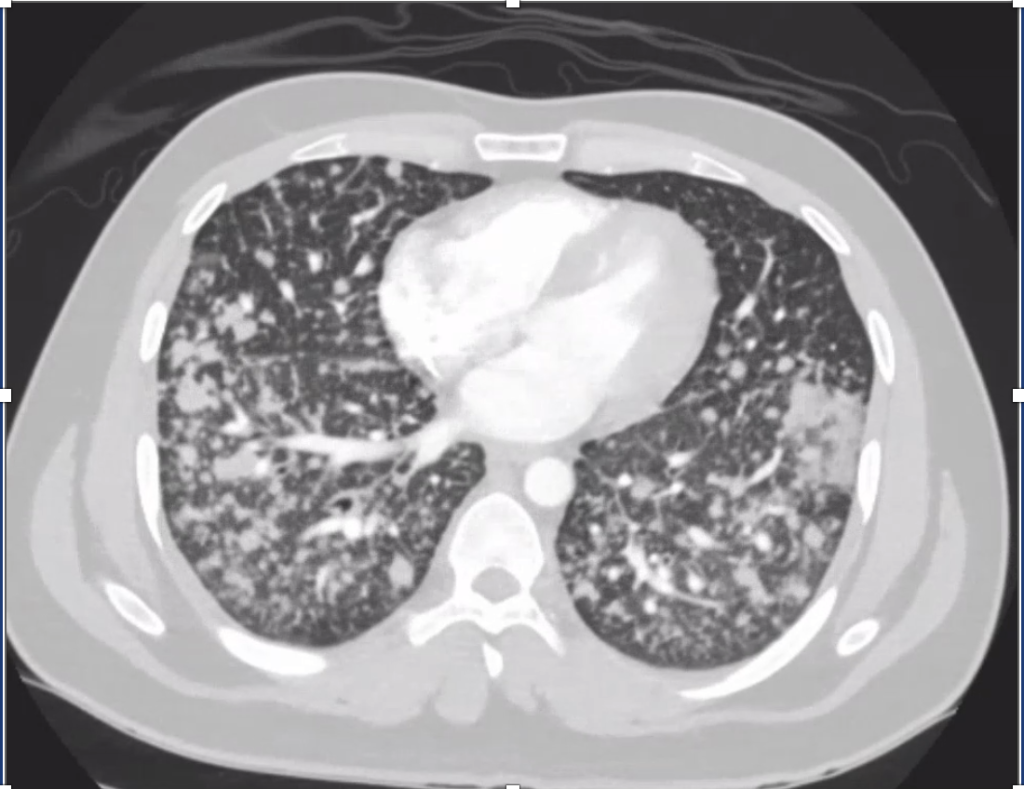

2) Imaging pearls—nodular pattern recognition

- Ask three things: craniocaudal distribution, symmetry, central vs peripheral.

- Centrilobular (spares pleura/fissures): airway-centered (e.g., NTM, bronchiolitis, tree-in-bud).

- Perilymphatic (tracks fissures/pleura & septa): sarcoid, lymphangitic spread.

- Random/diffuse (involves pleural surfaces): hematogenous spread → think miliary TB, disseminated fungal, septic emboli, metastatic disease.

- Interval change matters: new cavitation and confluence can upweight infection or aggressive malignancy.

- Therapy: Targeted TKI (crizotinib) → dramatic radiographic response of miliary lung disease and CNS lesions.

- Teaching point: even “miliary TB-like” lungs + CNS lesions in a 20-something can be driver-positive lung cancer—don’t let age or pattern blind you.